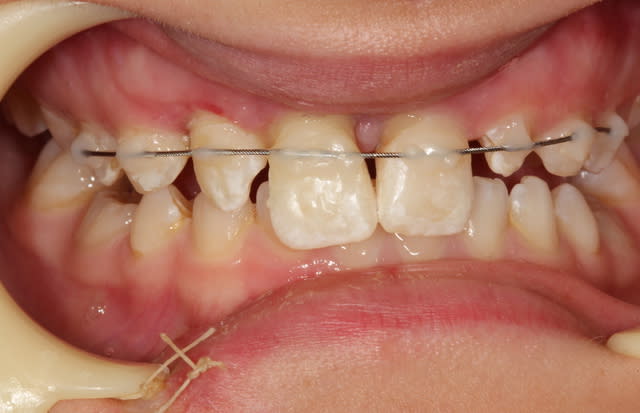

Ne mets pas la 21 dans la contention qui n'a d'intérêt que pour stabiliser la dent reimplantée. Tu as une cotation équivalente à SC40 pour cela.

Je sens pas du tout la contention étendue: pas de canine, la 21 légèrement lingualée suite au choc et la 11 en céram.

Je pars du principe qu'il faut une contention sur une période courte, Votre avis? une ou deux semaines. Le gosse prend l'avion dans 1 semaine.

Je vois 2 options : je réalise en thermoformage un nightguard sur la mandibule, épais,affiné au regard des 31-32 33 à porter 24/24 sauf les repas semi liquides durant 1 ou deux semaines avec contention 21-22 à faire sauter dans une à deux semaines

Sinon, deuxième option: toujours contention 22-21 et je modifie la face palatine de la 11 pour lui donner un bombé protégeant cette position lingualée de la 21 durant 1 semaine et dans une semaine je retravaille en bouche cette face palatine qui aura un polissage mécanique et non un glaçage et je fais sauter la contention.